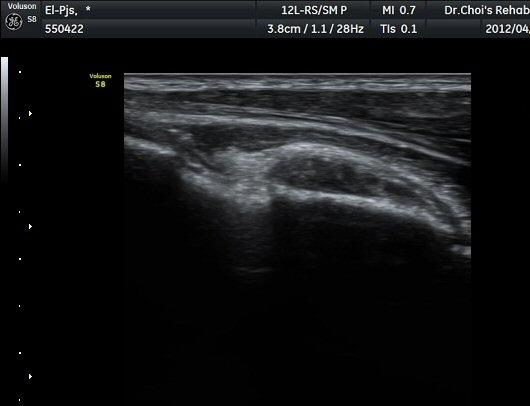

¾Æ·§ÆÈÀ» ¿ÏÀüÈ÷ ȸ³»ÇÑ »óÅ¿¡¼­ ÆÈ²ÞÄ¡°üÀý 1.5cm ¾Æ·¡¿¡ ŽÃËÀÚ¸¦ ȾÀ¸·Î ´ë´Ï ¿ä°ñ°ú

ºñ°ñÀÌ °üÂûµÇ°í ±× »çÀÌ¿¡¼­ À̵ιڱ٠ÈûÁÙ ºÎÂøºÎ°¡ °üÂûµÈ´Ù(±×¸² 7). ŽÂÊÀÚ¸¦ Á¾´Ü¸éÀ¸·Î

À§Ä¡ÇÏ´Ï ¿ä°ñµ¹±â¿¡ ºÎÂøµÈ À̵ιڱ٠ÈûÁÙÀÌ ¶Ñ·ÈÈ÷ °üÂûµÈ´Ù(±×¸² 8).